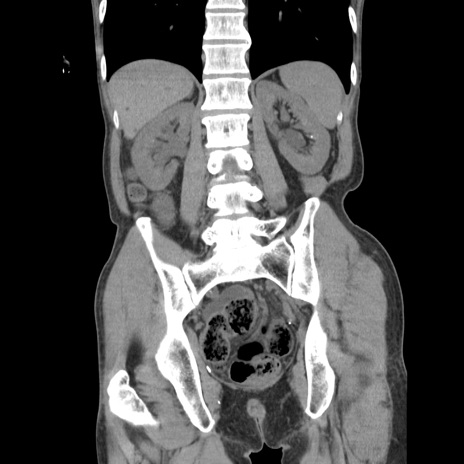

横断像

【症例】 60歳代男性

【主訴】 下腹部痛

【現病歴】 本日夜中より下腹部痛の症状認め、受診。

【既往歴】 膀胱癌(膀胱全摘+尿管皮膚瘻術) 、胃癌術後

【身体所見】 BT 35.3℃、PR 58/min、BP 136/98mHg、腹部平坦、軟、腸蠕動音±、ストマ留置あり、左上腹部~正中部に圧痛あり、反跳痛なし。

【データ】WBC 5100、CRP0.01